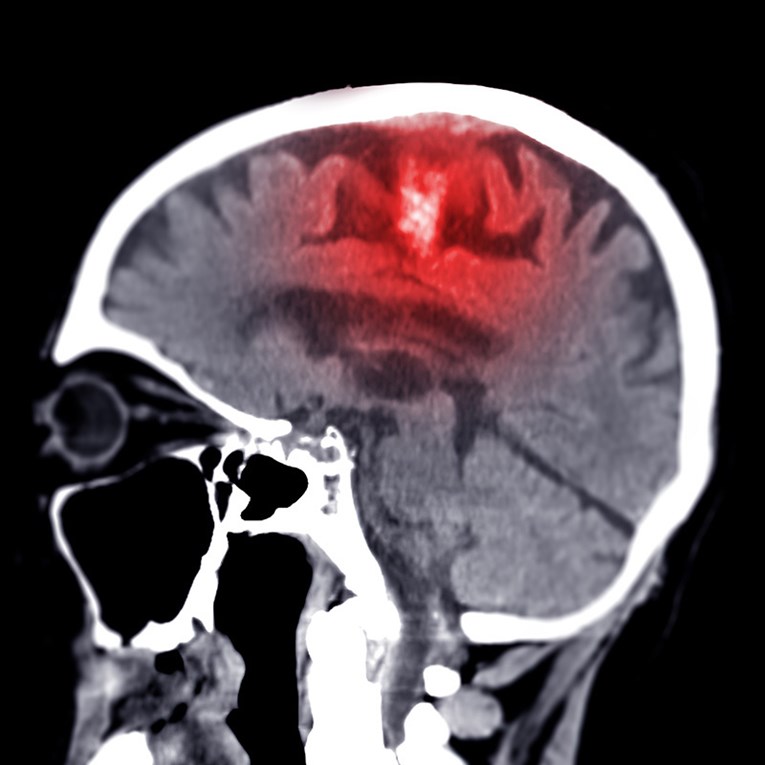

Двете групи глувци развиле оштетување на мозокот многу слично на она што се гледа кај Алцхајмеровата болест. Бариерата што нормално го штити мозокот од штетни супстанции почнала да протекува, нервните влакна постепено се распаднале, а мозокот развил долготрајно воспаление. Во исто време, способноста за создавање нови мозочни клетки во делот од мозокот важен за меморијата била ослабена, а комуникацијата меѓу нервните клетки се влошила. Сето ова било придружено со обемно оштетување на клетките. Како резултат на овие промени, глувците имале сериозни проблеми со меморијата, учењето и ориентацијата, многу слични на оние што ги доживуваат луѓето со Алцхајмерова болест.

Резултатите беа изненадувачки. Одржувањето на рамнотежата на NAD+ ги заштити глувците од развој на Алцхајмерова болест, а лекувањето на животни со напредна болест му овозможи на мозокот да ја поправи големата штета предизвикана од мутациите. Во двата модели, глувците целосно ги повратија своите когнитивни способности.

Опоравувањето беше придружено и со враќање на нивоата на тау-протеин 217 во крвта на нормални вредности. Ова дополнително потврди дека болеста навистина е поништена, бидејќи тау-протеинот 217 е биомаркер за Алцхајмерова болест кај луѓето.

Подобрувањето се базира на запирање на губењето на невроните, зголемена синаптичка пластичност, како и на поголемото значење на младите неврони што се формираат во мозокот на глушецот. Авторите на трудот го нарекуваат ова отпорност на мозокот на оштетување и тврдат дека подобрувањето на симптомите не мора нужно да биде поврзано со враќањето на изгубените неврони, туку дека отпорниот мозок го компензира ова со прилагодување кон добиената штета“, објаснува Гајовиќ.